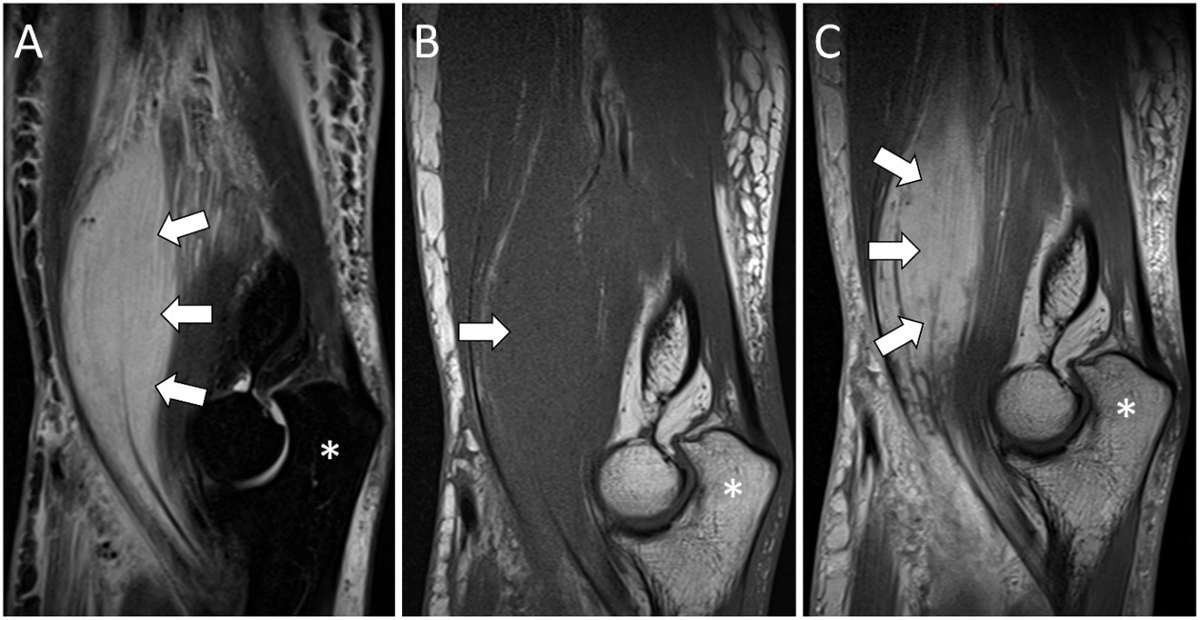

Figure 2

Sagittal MRI images of PM (white arrows) in the right brachialis muscle: hyperintense on STIR images (A), isointense compared to the muscle on T1WI (B), and a marked enhancement on post-contrast T1WI (C). Olecranon (*).